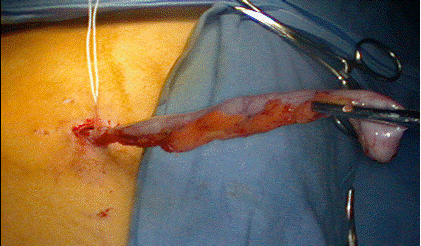

Extragerea apendicelui

Apendicele poate fi extras printr-un sac special sau prin canula de 10 mm, fara sa se contamineze peretele abdominal. Daca apendicele este voluminos, se poate folosi o canula de 12 mm care se introduce pe locul trocarului de 10 mm. Sacul se poate confectiona si dintr-un deget de manusa chirurgicala. Daca pentru extragerea apendicelui este necesara largirea aponevrozei, la sfarsitul interventiei aceasta va fi inchisa cu un fir resorbabil.